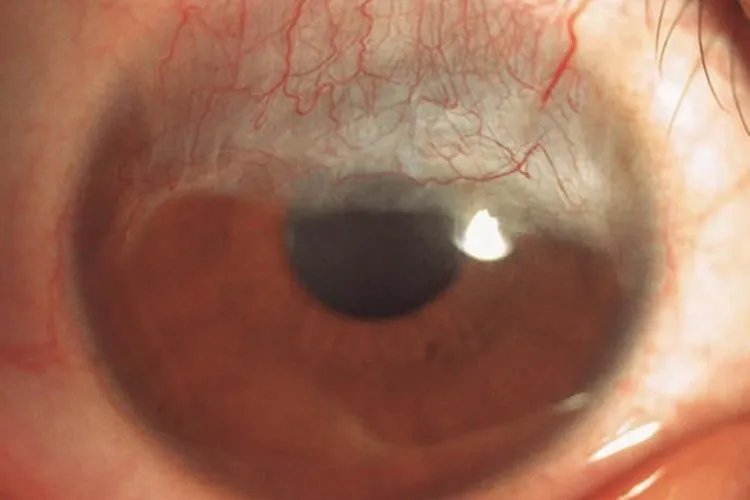

神经麻痹性角膜炎病变早期,暴露于睑裂部位的角膜上皮出现点状脱落,逐渐扩展成片状上皮缺损,甚至出现大片无上皮区域,继之形成溃疡。

暴露性角膜炎初期角膜、结膜上皮干燥、粗糙,暴露部位结膜充血、肥厚,角膜上皮由点状糜烂逐渐融合成大片的缺损,新生血管形成。